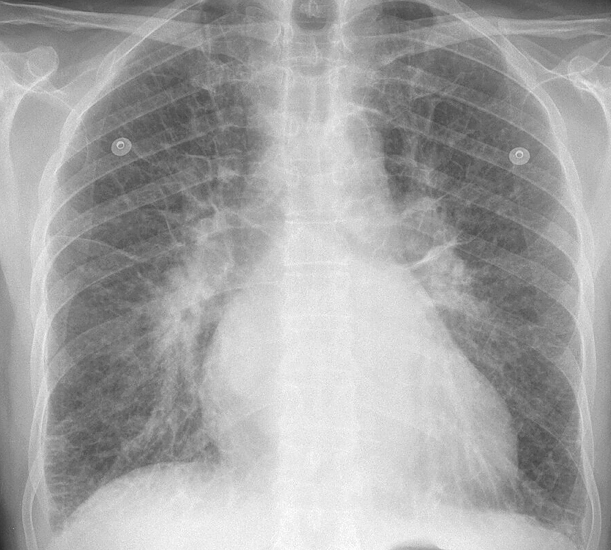

Gallery Cardiac Heart failure IPE 1

IPE 1